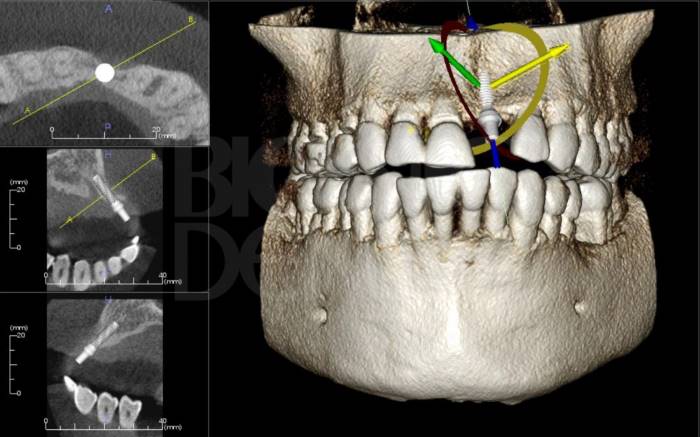

Дентальна комп’ютерна томографія (КТ) — це діагностична процедура в сучасній стоматології. Її результат дозволяє терапевту достовірно оцінити стан та анатомічні особливості кореневих каналів, локалізувати запальний процес. Ортопед може побачити точне розташування, будову СНЩС, імплантолог — оцінити параметри щелепної кістки, структуру, щільність та об’єм.

3D знімок — точний метод діагностики, лікар отримує повну інформацію про стан щелепно-лицьового апарату пацієнта, гайморових пазух. Отримані в результаті сканування знімки дають можливість стоматологу збільшувати, повертати і досліджувати під кутом області, що цікавлять, що неможливо при рентген-дослідженні. Також комп’ютерна томографія вимірює висоту, ширину кістки, визначає тип. Це потрібно, щоб підібрати розмір та тип імплантату при плануванні операції.

Томографія перед імплантацією дозволяє:

• виявити приховані каріозні порожнини сусідніх зубів, викривлення, довжину каналів  для складання плану лікування перед імплантацією;

• виявити ретиновані, надкомплектні зуби, які можуть заважати встановленню імплантатів;

• оцінити кісткові перегородки, області патологічної перебудови кісткової тканини;

• візуалізувати запалення, кісти, гранульоми, абсцеси зубів поруч із планованою зоною імплантації, які необхідно вилікувати перед операцією;

• виявити запалення у гайморових пазухах та слізних каналах, які можуть стати тимчасовою перешкодою до імплантації;

• оцінити параметри кісткової тканини — об’єм, щільність, ступінь резорбції, нахил альвеолярного відростка, товщину кортикальних пластин, щоб правильно підібрати розмір та форму імплантату;

• уточнити анатомічну будову верхньощелепних синусів, нижньощелепного каналу та інших кісткових структур, щоб спланувати кут нахилу при встановленні штучного стрижня;

• виявити аномалії зубощелепної системи, патології скронево-щелепного суглоба для правильного моделювання ортопедичної конструкції на імплантат;

• проконтролювати якість встановлення імпланту, коронки;

• оцінити густину кістки навколо встановленого імплантату;

• уточнити тяжкість отриманих пошкоджень, якщо відновлюється зубний ряд після травми.

Ортопантомограма — це швидше допоміжний діагностичний інструмент, що надає оглядову картину і виявляє явну патологію. На відміну від панорамного знімка, 3D комп’ютерна томографія дає не одне плоске зображення щелепи. Лікар отримує низку послідовних зображень у різній проекції без спотворень, властивих панорамного знімка. Отримане тривимірне зображення дозволяє лікарю розглянути щелепно-лицьову зону на будь-якій глибині з усіх боків та кутів. Приклад: на панорамному знімку видно правильний імплант, а на КТ дослідженні виявлені помилки при встановленні.

Дослідження проводиться за допомогою стоматологічного комп’ютерного томографа. Жодної попередньої підготовки процедура не передбачає.

Для виконання 3D знімка пацієнта просять закусити зубами спеціальну закусочну пластину і зафіксувати положення за допомогою фіксуючої опори. Протягом 15-30 секунд слід дотримуватися нерухомості.